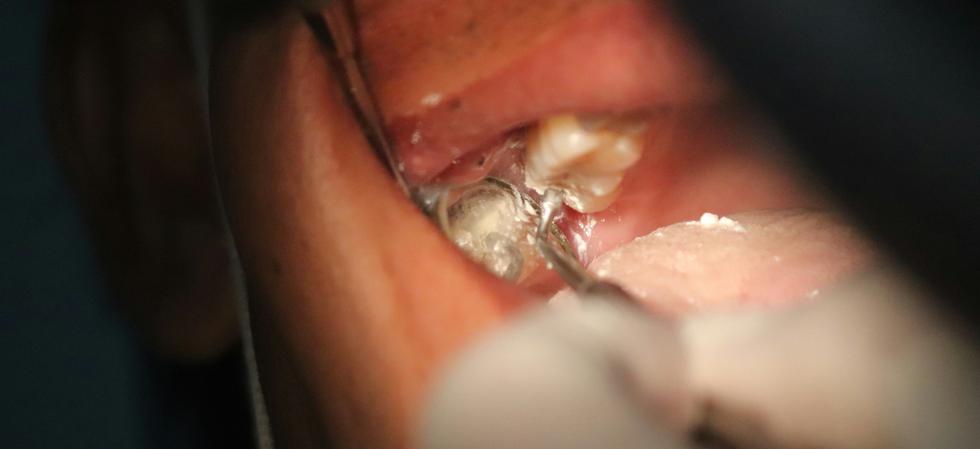

Större stenar: Kräver ibland att läkare avlägsnar stenen genom ett mindre kirurgiskt ingrepp.